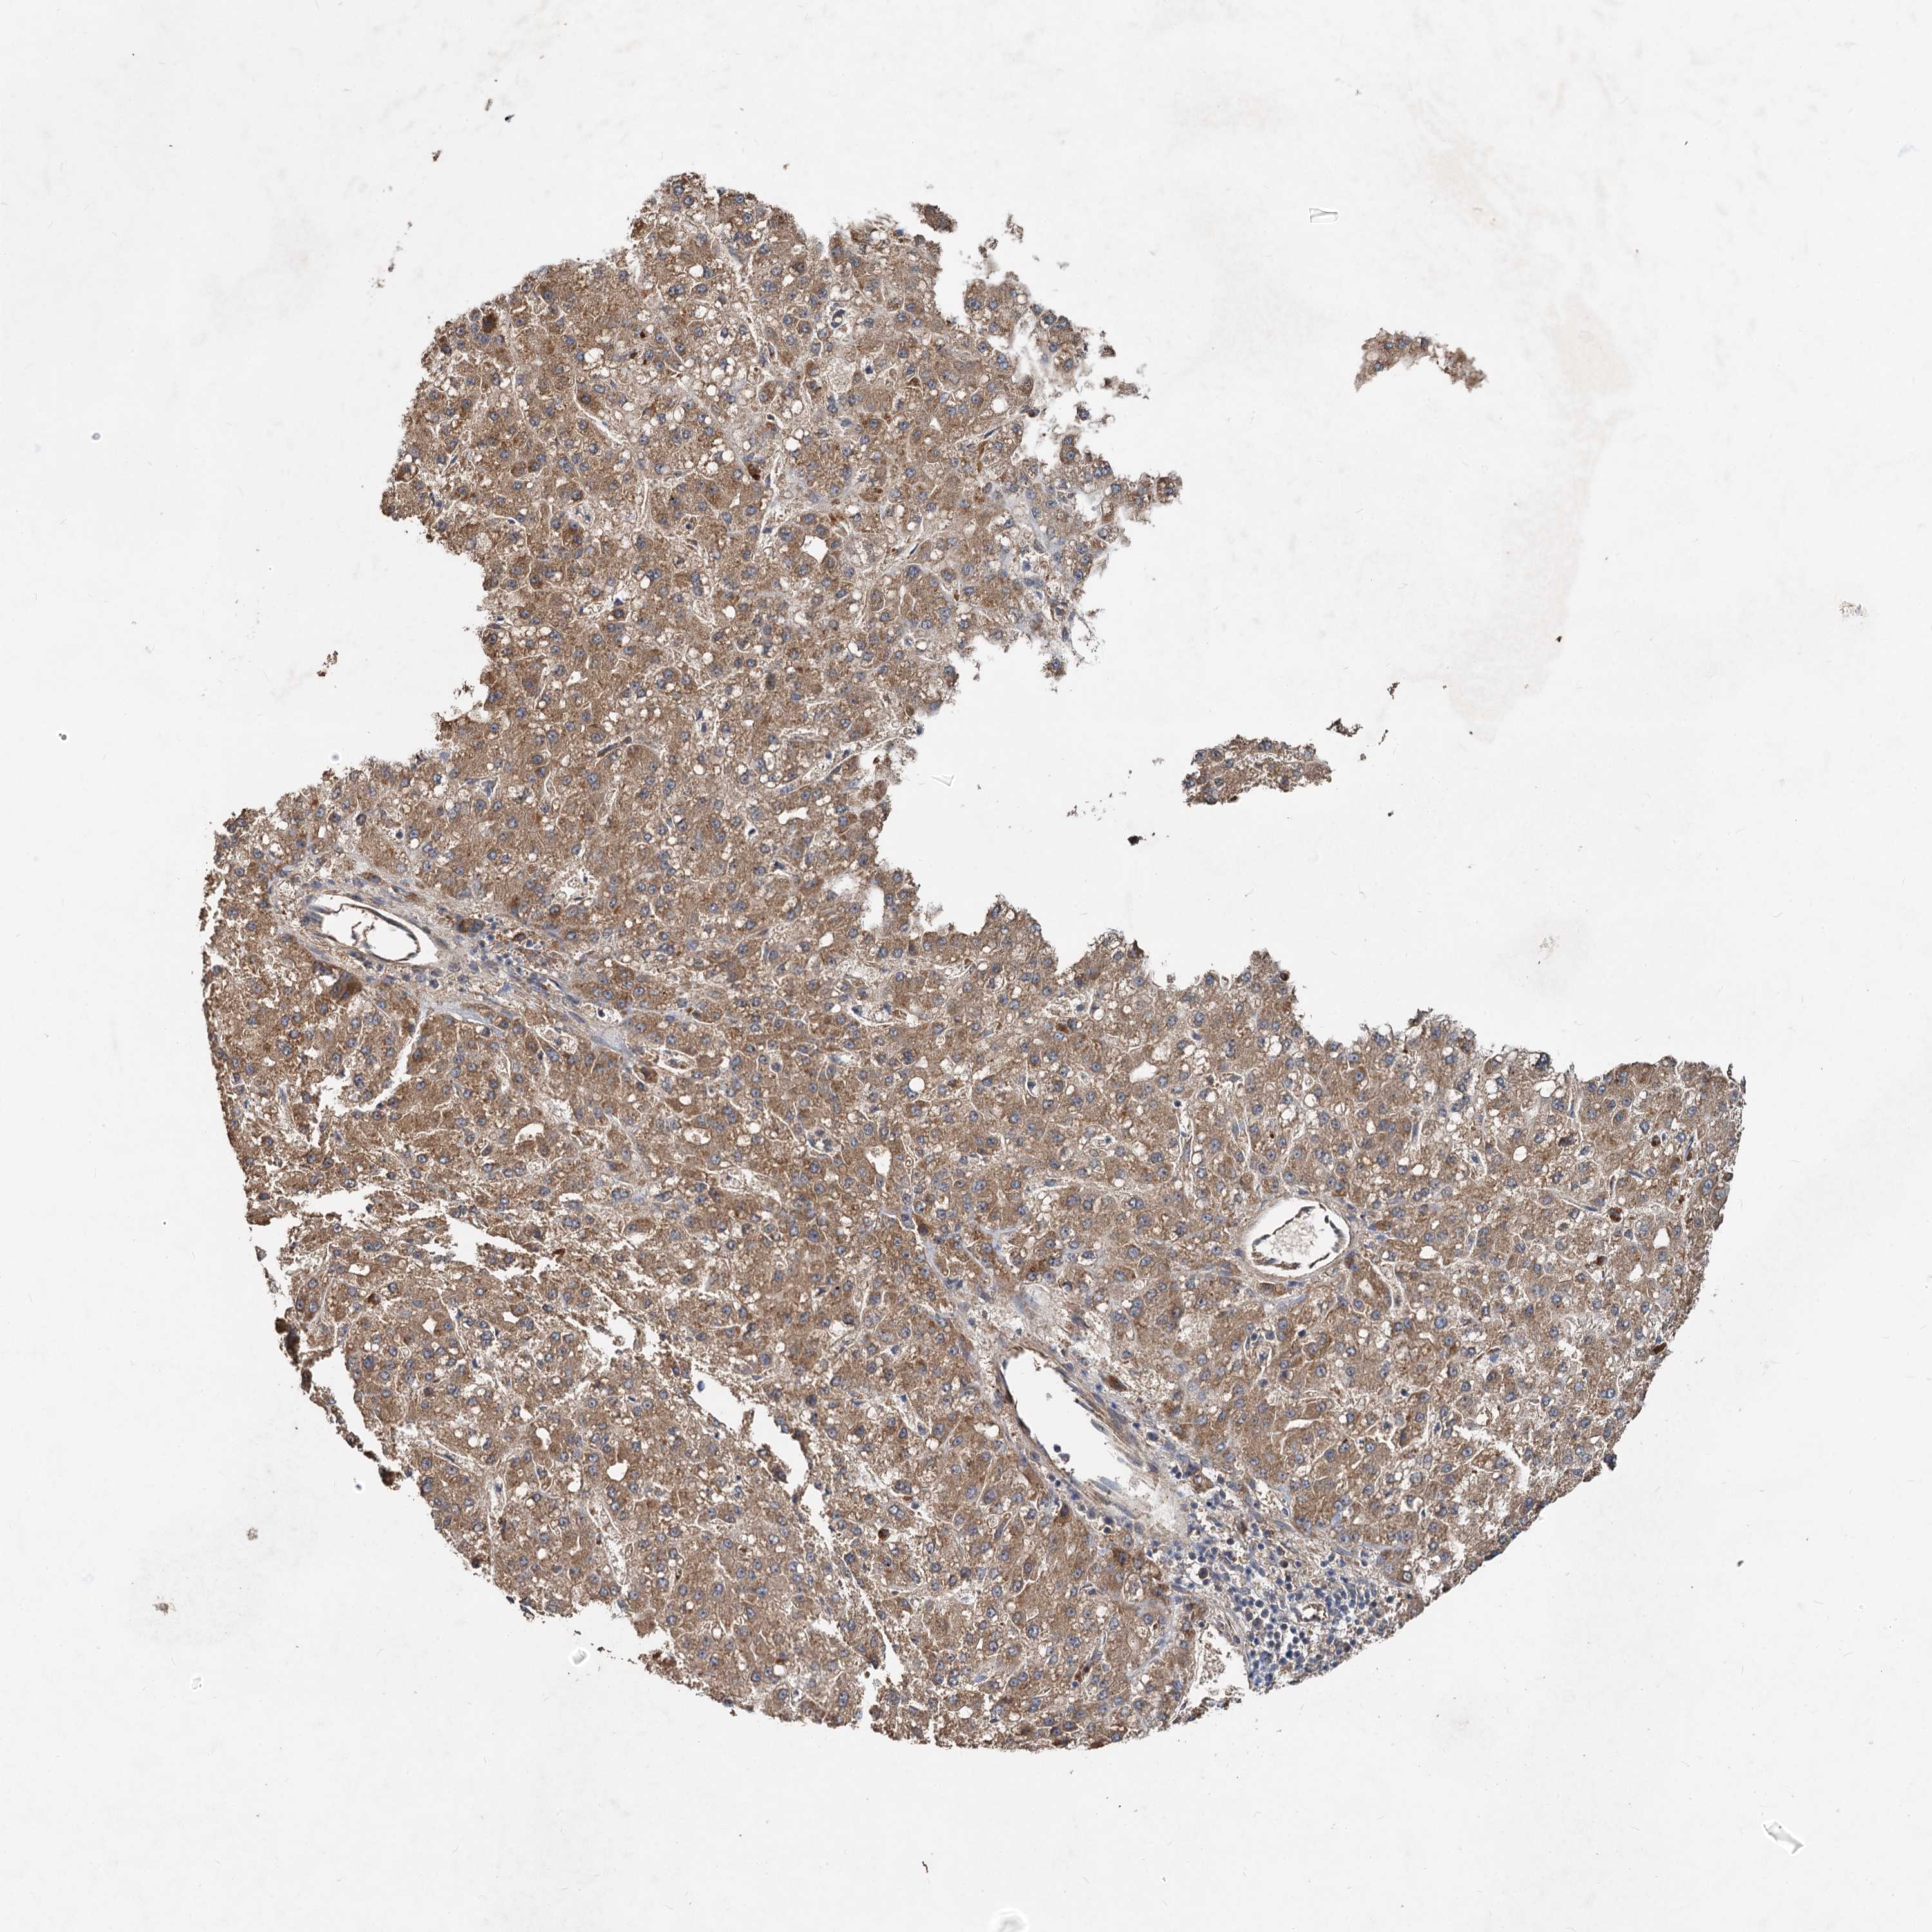

LIVER CANCER - Protein expressioni

A mouse-over function shows sample information and annotation data. Click on an image to view it in a full screen mode. Samples can be filtered based on level of antibody staining by selecting one or several of the following categories: high, medium, low and not detected. The assay and annotation is described here.

Note that samples used for immunohistochemistry by the Human Protein Atlas do not correspond to samples in the TCGA dataset.

Antibody stainingi

Antibody staining in the annotated cell types in the current human tissue is reported as not detected, low, medium, or high, based on conventional immunohistochemistry profiling in selected tissues. This score is based on the combination of the staining intensity and fraction of stained cells.

Each image is clickable and will lead to virtual microscopy that enables deeper exploration of all samples and also displays staining intensity scores, fraction scores and subcellular localization as well as patient and tissue information for each sample.

Antibody HPA040092

Staining

High

Medium

Low

Not detected

Intensity

Strong

Moderate

Weak

Negative

Quantity

>75%

75%-25%

<25%

None

Location

Nuclear

Cytoplasmic/membranous

Cytoplasmic/membranous,nuclear

Cholangiocarcinoma

Carcinoma, Hepatocellular, NOS